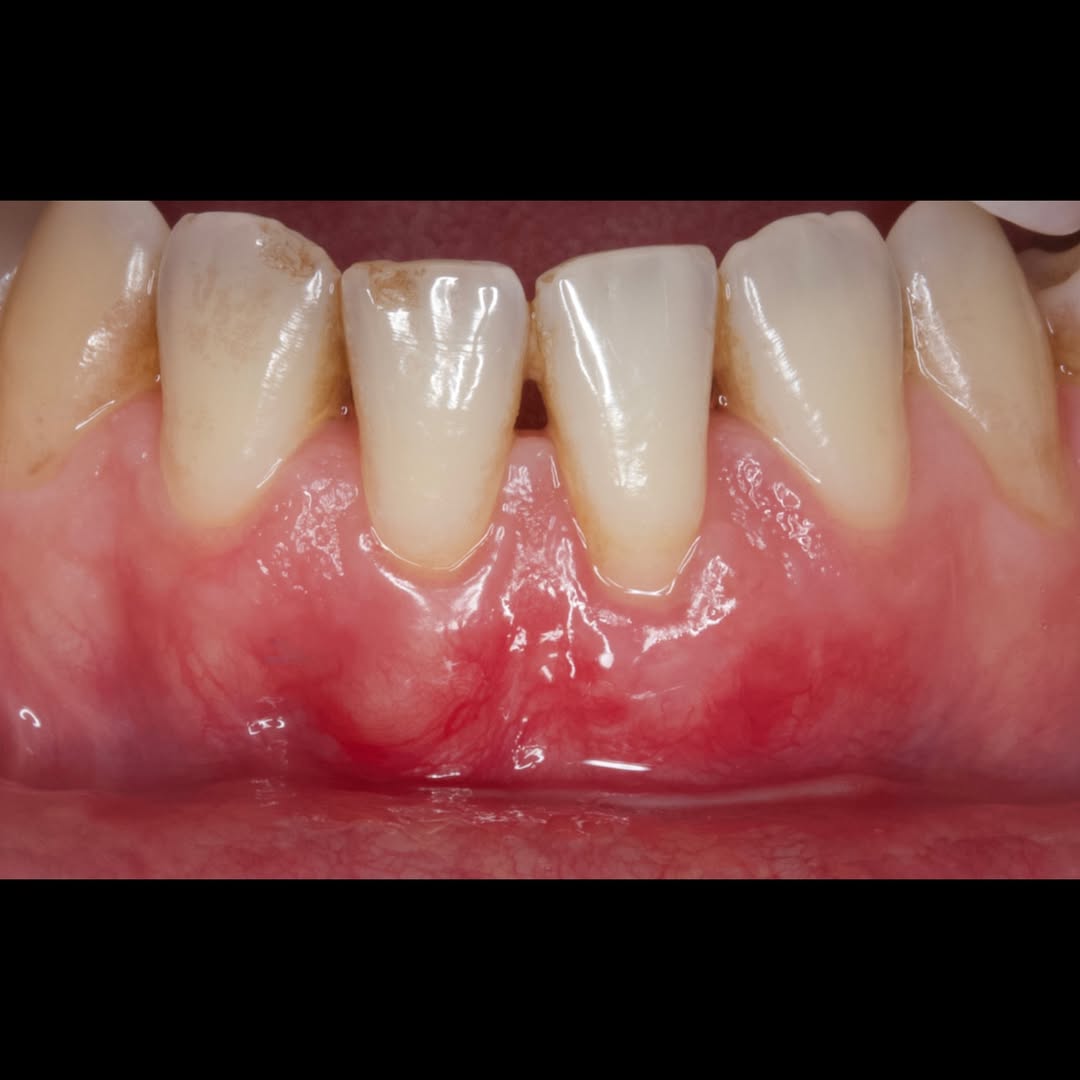

Durante una mañana, asistirás a una Cirugía Mucogingival de recubrimiento radicular de una recesión unitaria en 31 con frenillo asociado. Gracias al uso del microscopio y a la proyección en tiempo real en pantalla, verás exactamente lo mismo que veo yo durante la cirugía, sin tener que estar

Una estancia clínica pensada para quienes quieran iniciarse o dar un paso más en el campo de la cirugía mucogingival. Durante esta experiencia tendrás la oportunidad de aprender en directo cómo se planifica y se lleva a cabo una cirugía mucogingival mediante técnica de Túnel.

La sesión